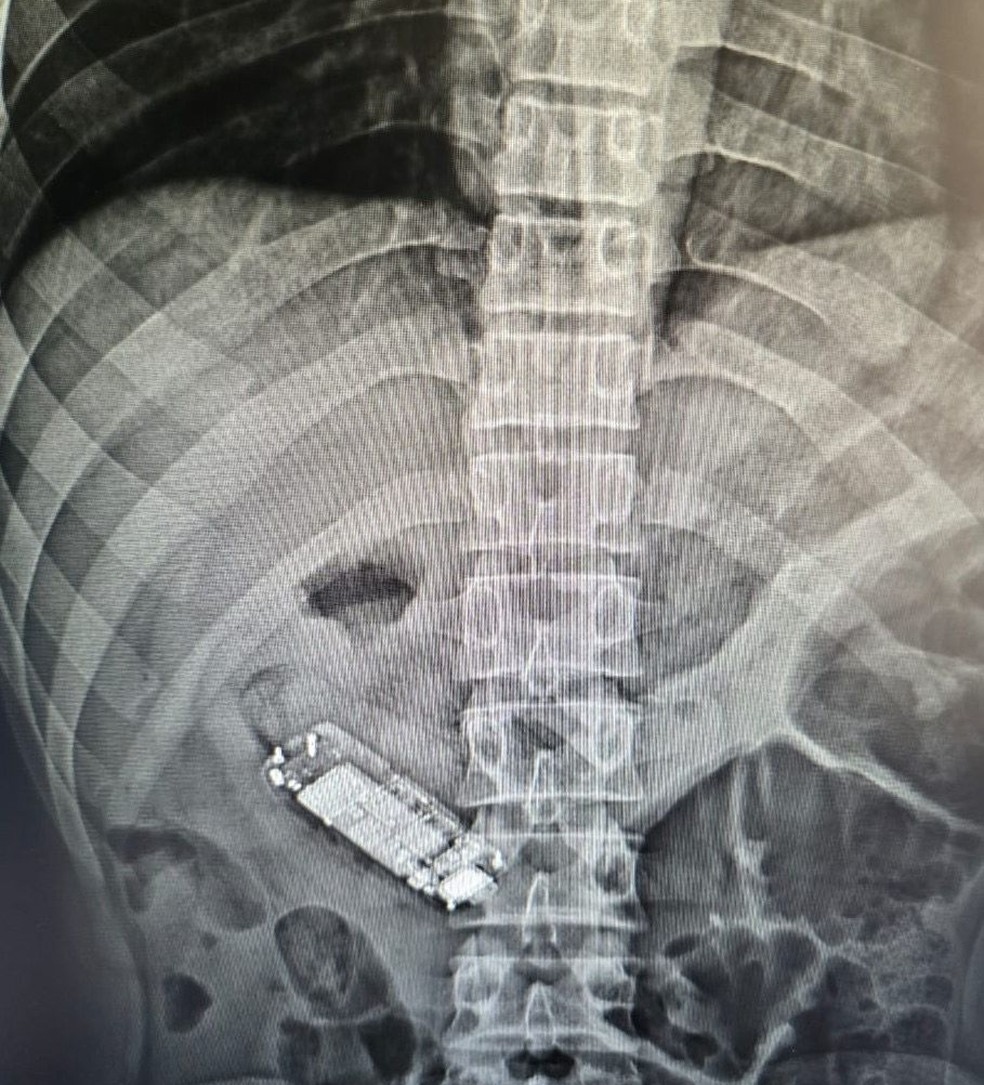

Preso reclamou de dores no estômago e, após ser levado para o hospital, um exame constatou que ele estava com o aparelho na barriga.

Ao passar por um exame de raio X, foi constatado que ele havia engolido um minicelular. Após o exame, o detento passou por uma cirurgia para a retirada do aparelho.